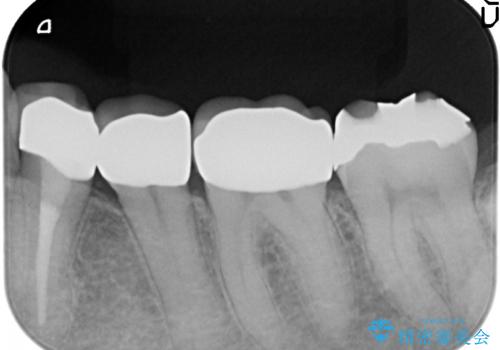

- 左下の詰め物が取れてしまったので治療したい、ついでに銀歯も白くしたいといらっしゃった方の症例です。

銀歯及び虫歯を除去後、オールセラミッククラウンによる補綴を行いました。

- オールセラミッククラウン…¥100,000×3、仮歯…¥10,000×3費用は治療当時の料金となります

今回用いたオールセラミッククラウンはジルコニアフレームという白い素材の上にセラミックを盛っているため、審美性が非常に高いのが特徴です。

また、ジルコニアは人工ダイヤモンドの材料にも使われているほど高い強度を持っており、そのためオールセラミッククラウンは審美性だけでなく、奥歯やブリッジの補綴も可能とするクラウンです。